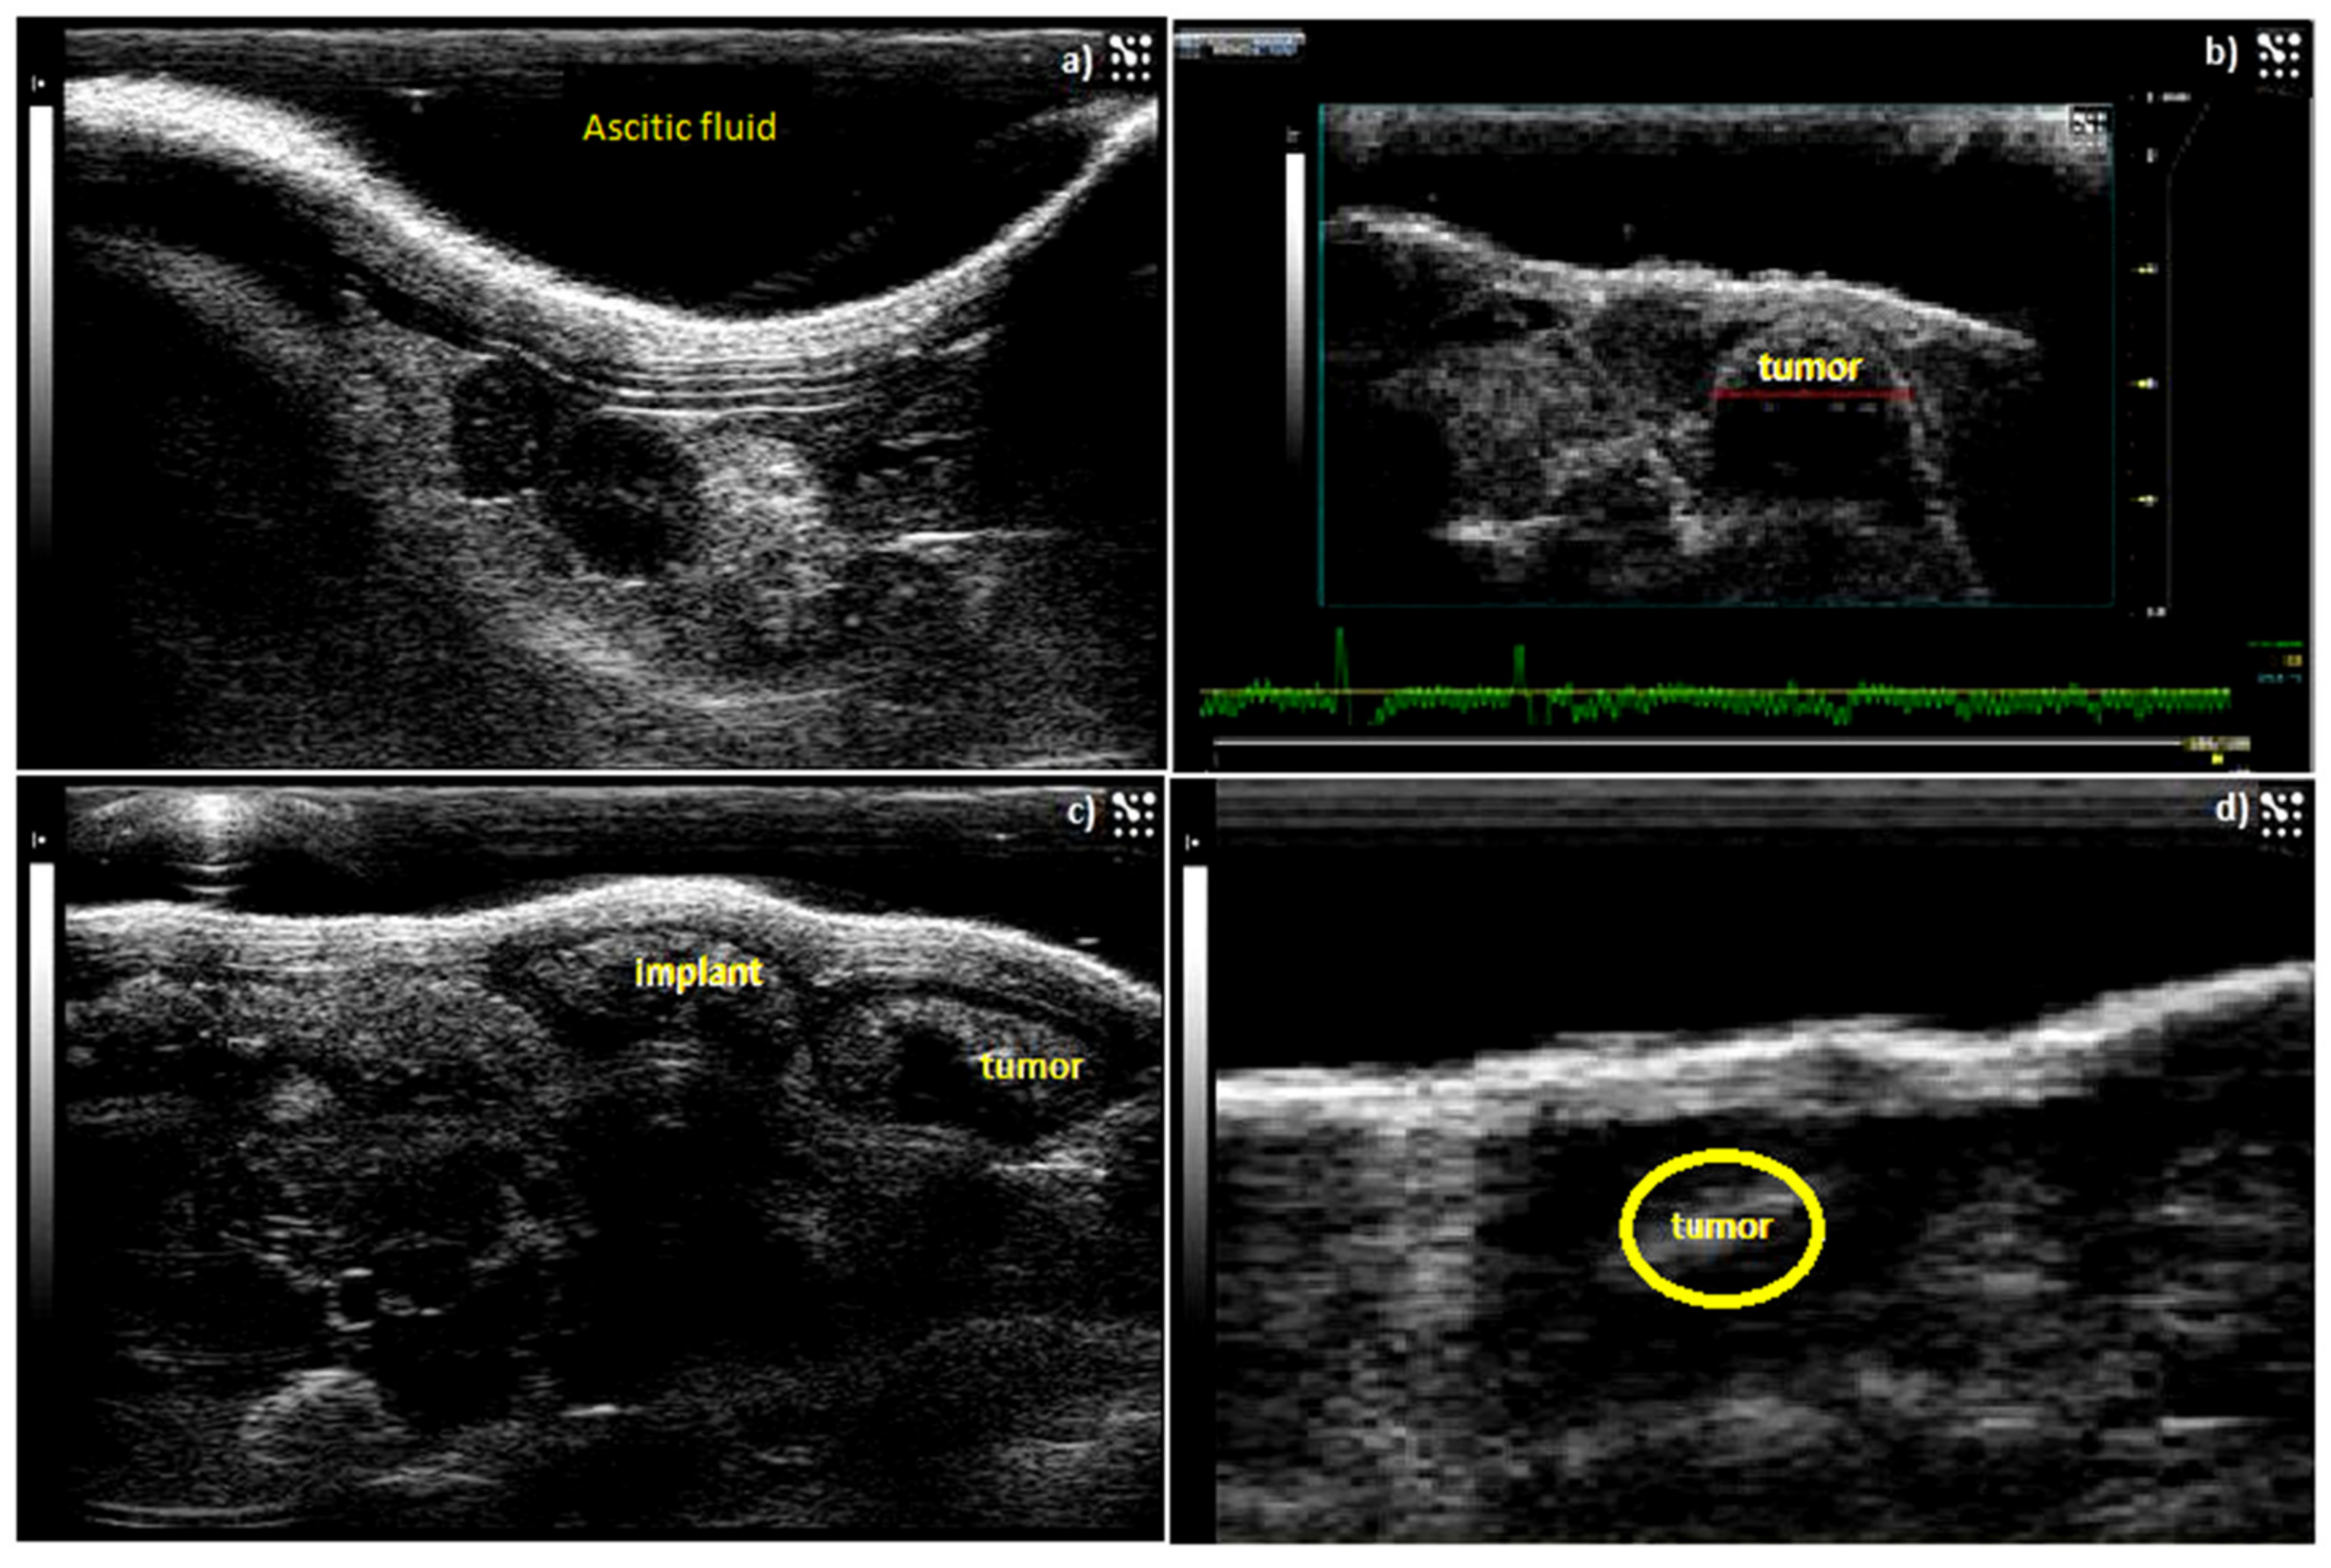

2.4.1. Induction of Human Ovarian Carcinoma in Athymic Swiss Nude Mice

4.5.4. IP-Inoculated Mice